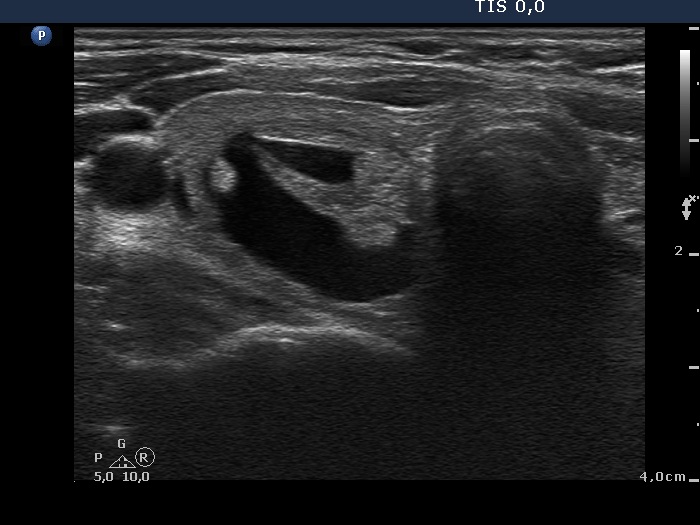

Ultrasonography. The thyroid was echonormal. There was moderately hypoechogenic nodule with blurred borders in the central part of the right lobe. A cystic nodule having echonormal solid part was found in the lower pole of the right lobe. The left lobe also has a cystic nodule.

Cytology of the moderately hypoechogenic nodule in the right lobe resulted in benign degenerative pattern. Two and 3 mL yellow fluid was removed from the cystic nodule in the right and left lobe, respectively. The cytology resulted in benign cystic degeneration in these cases.